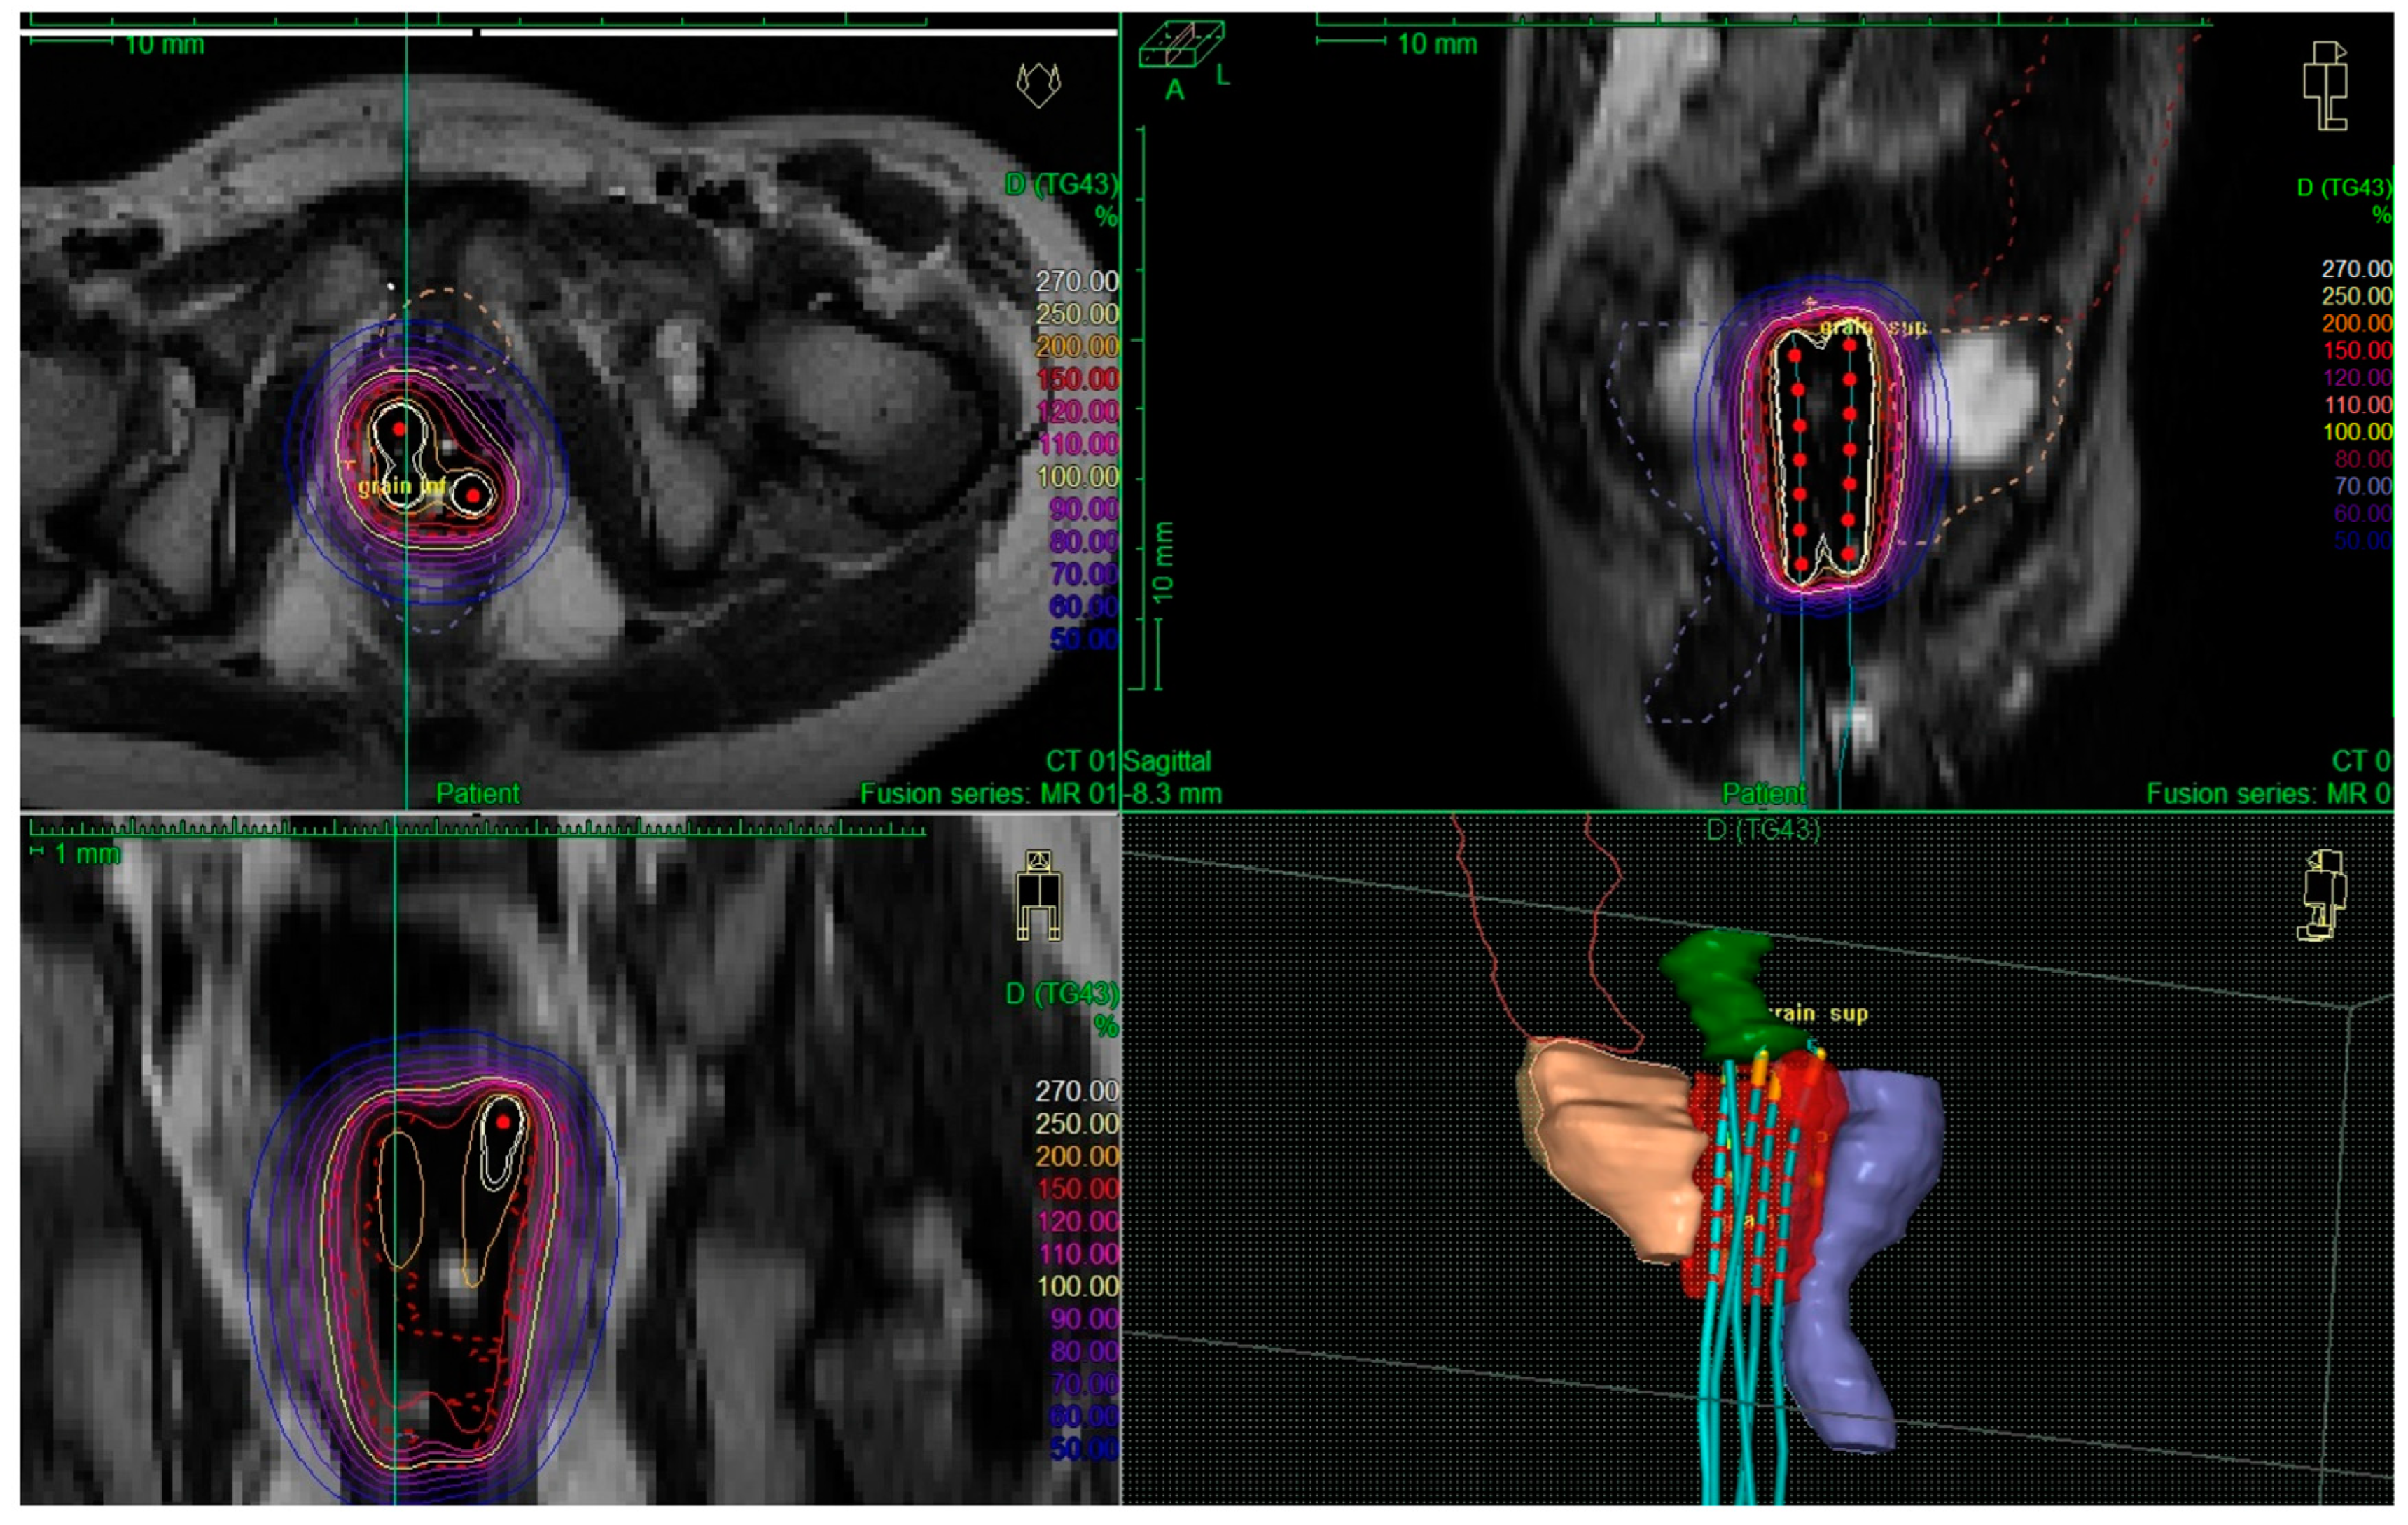

Dose was initially prescribed to the external part of the vaginal wall at the mid-level of the implant. Then, dose optimization was performed through dwell times and position modifications to keep organs at risk doses as low as possible, without specific dose/volume constraint. It was aimed that the 100% isodose did not overlap with organs at risk volumes, especially at the level of the anterior rectal wall and that volumes of the vaginal wall receiving 150% isodose were as minimal as possible. An example of dose distribution is shown in Figure 1. Irradiation was delivered with an Iridium-192 source, and the total dose was delivered through hourly pulses of 0.42 Gy per pulse to keep the daily dose at 10 Gy. Doses to the tumor and to organs at risk were reported after conversion into EQD2 (equivalent dose per 2 Gy fractions, α/β value = 10 Gy for CTV and 3 Gy for organs at risk). Usual precautions for pediatric PDR treatments were followed, as previously reported for bladder prostate RMS treatments [5]. Briefly, the parents had information on radioprotection rules. They were not allowed to stay in the brachytherapy department overnight. A daily examination was done by dedicated radiotherapy technicians to ensure that there was no applicator displacement. In case of any doubt, radiographs or CT scans were acquired to check for the applicator position. A pediatrician visited the patient daily and more frequently, if specifically required, to prescribe analgesics and soft-conscious sedation if required.

Figure 1. Example of an image-guided treatment for a 2-year-old girl with vaginal rhabdomyosarcoma. At the time of brachytherapy, there was multifocal residual disease involving the left and posterior parts of the vagina. An intracavitary procedure was performed with a vaginal mold applicator (four catheters). The CTV is red, the bladder is orange, and the rectum is blue. The 100% isodose (60 Gy isodose) is shown in yellow.